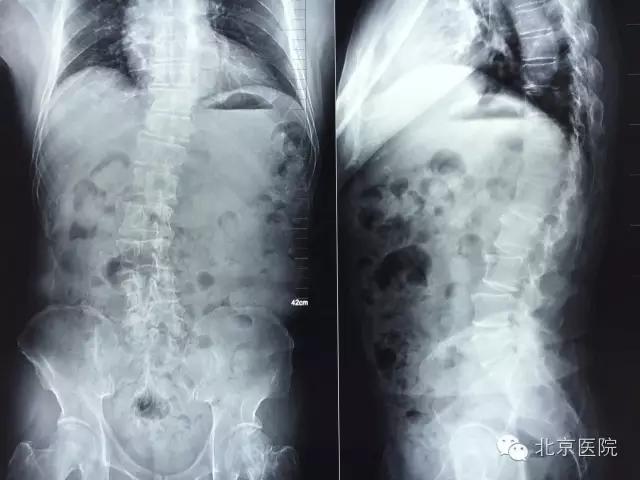

近日,北京医院骨科成功治疗一名合并小儿麻痹症的脊柱侧弯患者。患者陈某某,男,62岁。年幼时因小儿麻痹症导致左下肢无力,主要靠右下肢行走。随着年纪增大,出现脊柱侧弯、腰疼,近年来腰疼逐渐加重伴右下肢放射痛,间歇性跛行小于100米,右下肢无法完成既往行走功能。到当地医院就诊,经针灸、理疗、药物等多种方法对症治疗无法缓解,后到北京医院骨科就诊。

患者由张啟维副主任医师接诊。他根据病情及临床资料诊断考虑患者属于小儿麻痹症后遗症导致的脊柱侧弯,随着年龄增大,脊柱侧弯发生退变并加重,导致椎管狭窄。椎管狭窄压迫神经导致患者出现腰疼及右下肢神经肌肉功能障碍。而患者由于小儿麻痹导致左下肢长期无力,如果其右下肢再出现神经肌肉功能障碍,今后将面临双下肢瘫痪,永远不能行走、坐轮椅的风险,手术治疗很必要。但患者合并糖尿病、高血压等内科疾病。既往有骨质疏松症导致的股骨颈骨折病史,病情比较复杂,客观上讲,麻醉及手术的风险较大。如手术过程出现意外,患者极有可能面临瘫痪的危险。因此,此手术极具挑战。

入院后,骨科闵楠医生带领住院医师团队积极完善各项检查,对患者进行术前安全评估及准备。张啟维副主任医师对患者进行了认真而仔细的查体,并结合病人症状及影像学资料为患者制定了一套安全有效的治疗方案。在方案制定过程中,张啟维副主任医师既考虑到充分减压以解除患者术前神经压迫症状,又考虑到对患者侧弯进行有效矫形以恢复脊柱力线平衡。同时,还要结合患者合并多种内科疾病、身体条件较差的实际情况,尽量在保证效果的前提下将手术小型化、微创化,以降低手术及麻醉给患者带来的创伤,进而降低手术麻醉风险。张啟维副主任医师结合自己出国学习所获得的先进技术,根据实际病情为患者制定了最适合的微创切开手术方案:即后柱截骨(PCO Posteiror Column Osteotomy)矫形联合腰椎4-5椎间融合加后路固定融合术。PCO后柱截骨术手术保留了椎板、棘突,既减少了手术神经、硬膜的损伤及出血,又为后柱植骨融合准备了良好的植骨床,也减少了临近节段退变几率,成为治疗侧弯畸形切开手术微创化的重要术式。是目前国际脊柱畸形手术微创化发展的重要成就之一。

此外,张啟维副主任医师还针对患者的骨密度及磁共振检查,对腰1椎体进行椎体成形强化,既治疗了腰1椎体血管瘤,同时又降低了长节段固定导致临近节段骨折及退变加速的风险,真正全面实现了个体化治疗方案。